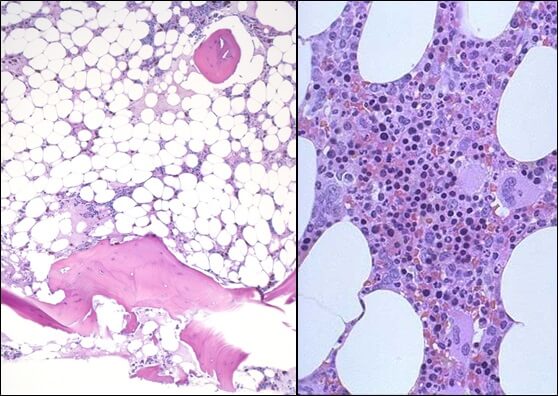

- Исследованиепунктата костного мозга. В миелограмме обнаруживается уменьшение количества миелокариоцитов и мегакариоцитов, снижение клеточности. В трепанобиоптате определяется замещение красного костного мозга жировым (желтым).

Привлекает внимание очень тяжелое течение этой формы у детей, картина носит острый характер и нередко смертельный исход наступает быстро. Гистологическое исследование выявило различную степень поражения костного мозга — от нормопластического аспекта вплоть до весьма тяжелой аплазии.

Гематологическая картина отражает наличие периферической панцитопении и нормоцитной или умеренно макроцитной анемий; показатель плодного гемоглобина бывает завышенным. При этом костный мозг представляется гипопластическим, жирным, иной раз нормо- или гипоцеллюлярным (Fanconi, Rohr Williams). Синдром видимо определяет рецессивный ген, в то же время цитогенетические исследования выявили большое разнообразие структурнохромосомных сдвигов (Bloom и сотр.). Описаны случаи, преобразовавшиеся в дальнейшем в острую лейкемию (Wintrobe).